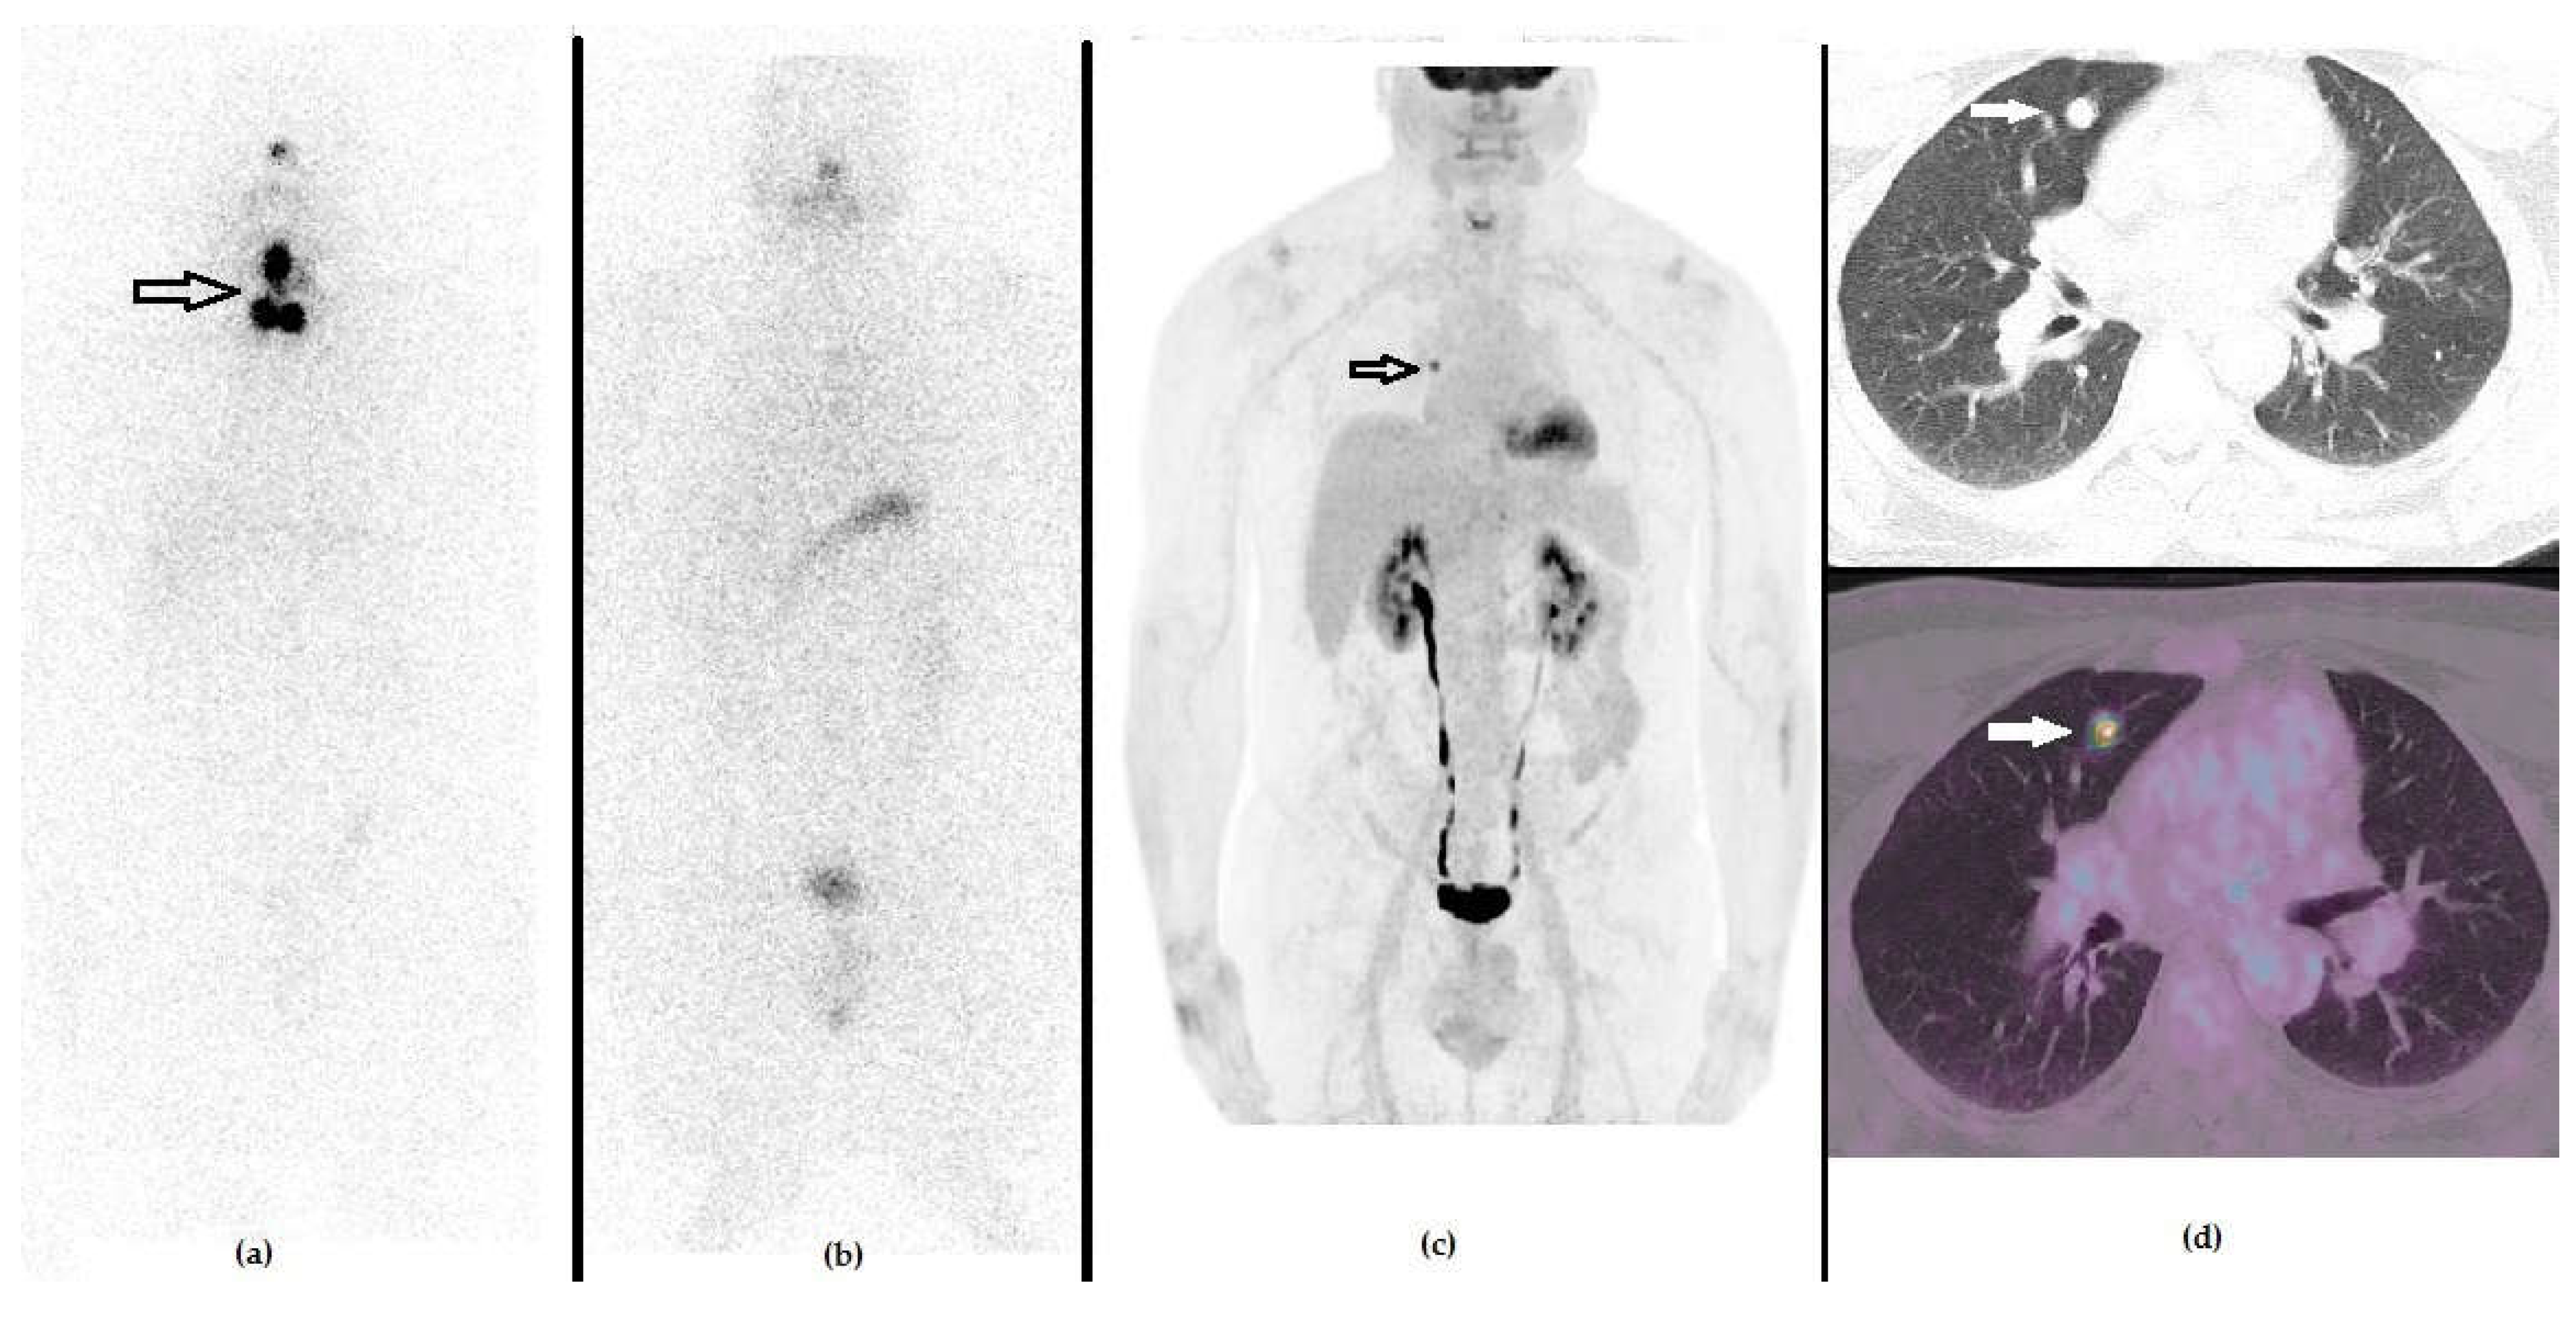

Figure 5. A 56-year-old male that previously underwent a thyroidectomy plus CND and 1 cycle of RAI due to Hürthle cell carcinoma (pT1b N1b). The first panel represents the post-RAI 131I-WBS showing the residual iodine-avid tissue in the anterior cervical region ((a), black arrow). Fifteen months after RAI, he presented with a slightly increased value of stimulated Tg serum level (i.e., 3.5 ng/mL), negative 131I-WBS (b) and neck US showing hypervascularized laterocervical node suspected of metastasis. (c) 18F-FDG PET/CT demonstrated a highly increased tracer incorporation in the suspected right laterocervical node, ((d) black arrow) also revealing metastases to the mediastinal nodes ((d), black bordered arrow), as evident in the whole body (d) and in the fused PET/CT axial images (e). The patient underwent surgery, followed by a further cycle of RAI.